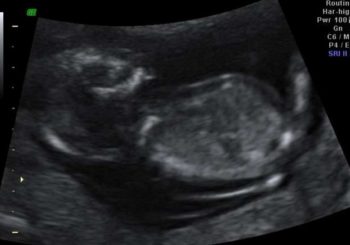

Ayrıntılı ultrason, detaylı ultrason ile aynı anlamdadır. Ayrıntılı ultrason gebeliğin 17-23 haftalarında uygulanabilir. Fakat sıklıkla 17.-18. haftalarda yapılır. Ayrıntılı ultrason yaklaşık 20-30 dakika sürer. Ayrıntılı ultrason sırasında bir şüphenin oluşması ya da bebeğin incelenemeyen organları için 3-4 hafta sonra tekrar ultrason yapılması önerilebilir. Ayrıntılı ultrason sırasında bir şüphe veya risk görülmemişse gebelik boyunca 1 kez ayrıntılı ultrasonun yapılması yeterlidir. Detaylı g...

Ultrasonografi USG (ultrasonografi) yıllardır tıp alanında yaygın olarak kullanılan bir tetkik yöntemidir. Bu işlem sırasında önce ilgili bölgeye jel sürülmekte ve daha sonra üstünde prob gezdirilmektedir. İstenildiği ya da hekiminizin önerdiği takdirde bu görüntüler çıktı şekilde hastaya da verilebilmektedir. Ultrason (USG) ile hem iç organlar hakkında bilgi edilebilir Gebelik tanı ve kontrolünde fetüsü izlemek amacıyla kullanılmaktadır. Bu tetkik gebeliğin özellikle ilk aylarında, 11. v...

Ultrason Nedir? USG (ultrasonografi) yıllardır tıp alanında yaygın olarak kullanılan bir tetkik yöntemidir. Bu işlem sırasında önce ilgili bölgeye jel sürülmekte ve daha sonra üstünde prob gezdirilmektedir. İstenildiği ya da hekiminizin önerdiği takdirde bu görüntüler çıktı şekilde hastaya da verilebilmektedir. Bu tetkikin pek çok avantajı bulunur. Ultrason (USG) ile hem iç organlar hakkında bilgi edilebilir, hem de gebelik tanı ve kontrolünde fetüsü izlemek amacıyla kullanılmaktadır. Bu ...

GEBELİK DÖNEMİNDE ULTRASON İNCELEMESİ Çağımızda ultrason gebelik muayenelerinin en önemli parçası olmuştur. Gebelikte hiç bir problem olmasa bile son yıllarda göze çarpan ve artan sıklıklarla ultrasonografi kontrolü yapılıyor. Gebeliğin farklı aylarında ultrasonla ayrıcalıklı değerlendirmeler yapılır. Örnek olarak gebeliğin ilk aylarında bebeğin kilosu ölçülemez yalnızca kalp atımı, kese büyüklüğü ve bunun gibi değerlendirmeler yapılır, gebeliğin 5. ayında kilosu, amniyotik sıvısı, plasentanı...